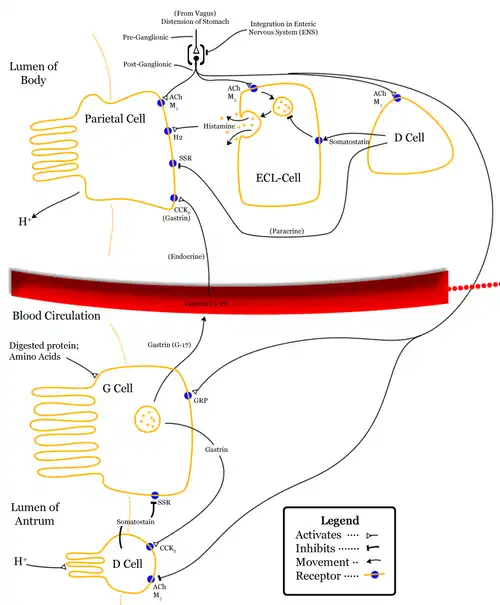

A parietal cell. | |

Control of stomach acid | |

Parietal cells (also known as oxyntic cells) are epithelial cells in the stomach that secrete hydrochloric acid (HCl) and intrinsic factor. These cells are located in the gastric glands found in the lining of the fundus and body regions of the stomach.[1] They contain an extensive secretory network of canaliculi from which the HCl is secreted by active transport into the stomach. The enzyme hydrogen potassium ATPase (H+/K+ ATPase) is unique to the parietal cells and transports the H+ against a concentration gradient of about 3 million to 1, which is the steepest ion gradient formed in the human body. Parietal cells are primarily regulated via histamine, acetylcholine and gastrin signalling from both central and local modulators.

Parietal cells secrete acid in response to three types of stimuli:[4]

- Histamine, stimulating H2 histamine receptors (most significant contribution).

- Acetylcholine (ACh), from parasympathetic activity via the vagus nerve and enteric nervous system, stimulating M3 receptors.[5]

- Gastrin, stimulating CCK2 receptors (least significant contribution, but also causes histamine secretion by local ECL cells).

Activation of histamine through H2 receptor causes increases in the intracellular cAMP level, while ACh through M3 receptor and gastrin through CCK2 receptor increases intracellular calcium level. These receptors are present on basolateral side of membrane.

Increased cAMP level results in increased protein kinase A. Protein kinase A phosphorylates proteins involved in the transport of H+/K+-ATPase from the cytoplasm to the cell membrane. This causes resorption of K+ ions and secretion of H+ ions. The pH of the secreted fluid can fall by 0.8.

Gastrin primarily induces acid-secretion indirectly, increasing histamine synthesis in ECL cells, which in turn signal parietal cells via histamine release and H2 stimulation.[6] Gastrin itself has no effect on the maximum histamine-stimulated gastric acid secretion.[7]

The effect of histamine, acetylcholine and gastrin is synergistic, that is, effect of two simultaneously is more than additive of effect of the two individually. It helps in non-linear increase of secretion with stimuli physiologically.[8]